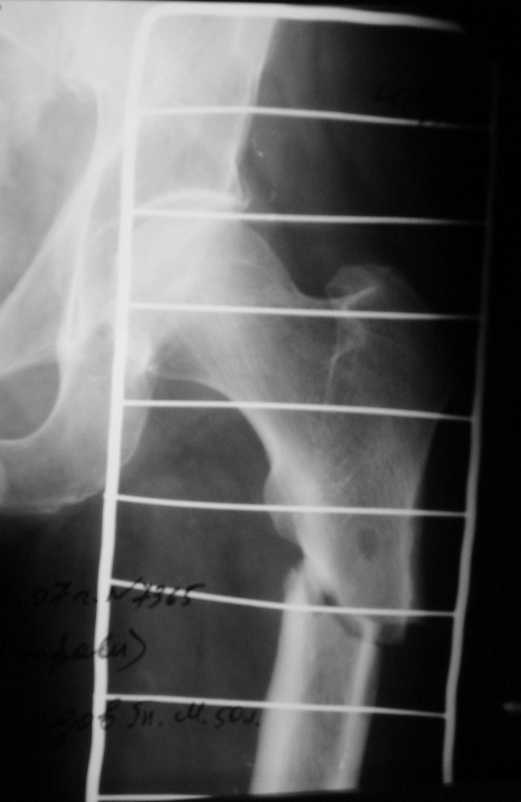

Больной М. 50-ти лет. Травма 21.07.2007г. Д/з: Перелом верхней 1/3 бедренной кости сосмещением.

Д/з: Перелом верхней 1/3 бедренной кости со смещением. В течении 20 лет страдаетраспространенным хроническим рецидивирующим актиномикозом левой нижней конечности. Вмае 2007г. перенес гнойно-некротическую флегмону левого бедра. В настоящее время на кожелевого бедра имеется множество свищевих отверстий покрытых корочками. 3 свищафункционируют, отделяемое серозно-гнойного характера. Находится на скелетномвытяжении. На Rg-грамме имеются изменеия бедренной кости в виде периостальной реакции имножественных просветлений на уровне диафиза. Целесообразность операции?

Больной М.5лет.Находится на лечении в травм. отделении по поводу патологический перелом в/3 диафиза левого бедра на фоне хронического рецидивирующего левой нижней конечности.R-снимки к сообщению.